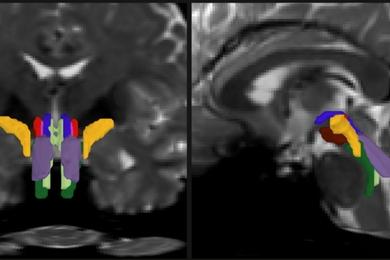

麻省理工学院(MIT)、哈佛大学和麻省总医院的研究团队开发了一款基于人工智能的软件,能够自动分割任何扩散MRI序列中的八个不同神经束。

作为博士论文的一部分,Olchanyi致力于开发一款AI算法来克服这些挑战。BSBT通过追踪来自丘脑、小脑等脑部邻近区域进入脑干的纤维束,生成“概率纤维图谱”。随后,一个卷积神经网络结合脑干内多通道成像信息,自动区分出八个独立的神经束。

为了训练神经网络,Olchanyi使用了人类连接组计划(HCP)中30例志愿者的活体扩散MRI扫描数据,并对其进行了手动标注,教会网络识别神经束。随后,他通过与尸检人脑的显微镜检查和超高分辨率成像结果对比验证BSBT的准确性。训练完成后,BSBT能够自动识别新扫描中的八个神经束。

研究团队将BSBT应用于阿尔茨海默病、帕金森病、多发性硬化和创伤性脑损伤患者的扩散MRI数据,比较患者与健康对照组,或患者自身随访数据。工具测量了神经束体积和“分数各向异性”(FA),后者反映水分子沿髓鞘轴突的流动程度,是白质结构完整性的指标。

结果显示,各疾病患者脑干神经束均出现一致的变化模式。阿尔茨海默病患者仅一束神经束显著下降;帕金森病患者三束神经束FA降低,另一束神经束体积在两年随访中减少;多发性硬化患者四束神经束FA下降,三束体积减少;创伤性脑损伤患者虽无显著体积损失,但大多数神经束FA降低。